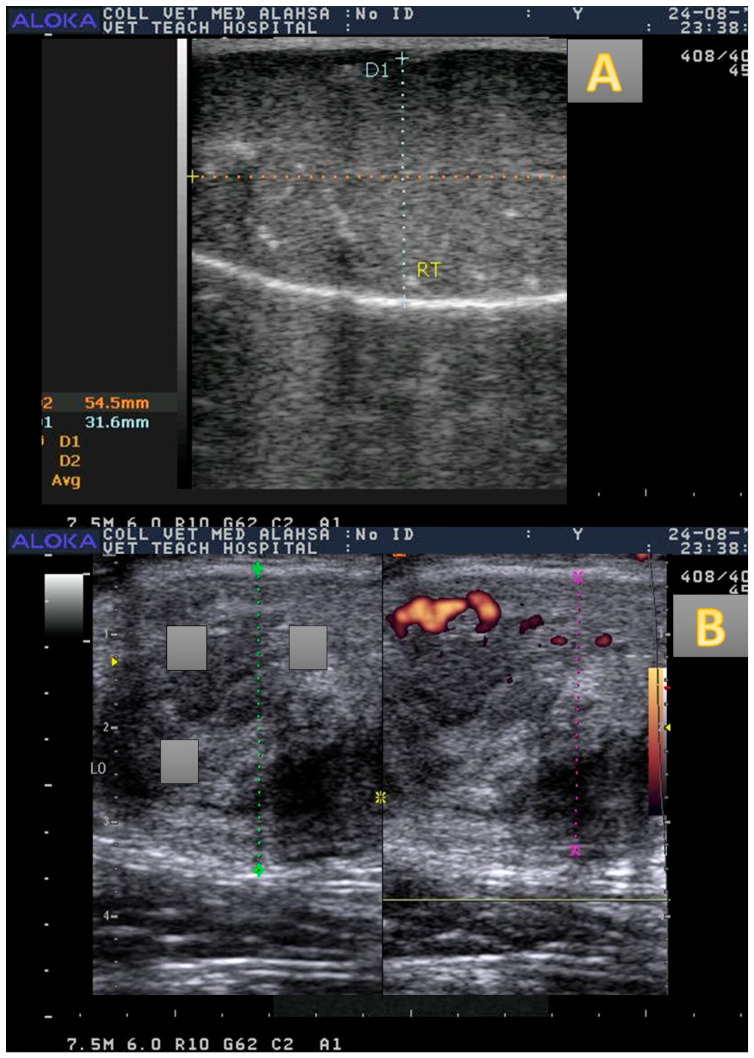

This study aims to demonstrate whether immunization against inhibin could alters testicular echotexture (TE), hemodynamics (resistance and pulstalilty index [RI and PI], testicular blood flow volume [TBFV]), and semen picture. Senile male camels were immunized actively against inhibin alpha subunit (immunized males; n = 5; subcutaneous route; 1 mL) or non immunized (control males; n = 5). The injection was four times with four weeks intervals. Semen was collected by electroejaculator once per week. Blood sampling, ultrasonography, and hormonal assaying was performed once per week. The levels of follicle stimulating hormone (FSH), luteinizing hormone (LH), estradiol (E2), testosterone (T), and nitric oxide (NO) were calculated. Regarding control camels, the FSH levels were elevated (p < 0.01) in immunized males weeks 6-9 in August. Both E2 and NO were increased in the same group at weeks 7-11 with the highest level in week 10 for E2 (17.01 ± 0.11 pg/mL) in September and in week 9 for NO (44.66 ± 0.15 µmol/L). The Doppler indices RI and PI were declined (p < 0.01) in immunized camels in weeks 7-11, while the TBFV was elevated (p < 0.01). A marked elevation (p < 0.05) in testicular volume was noticed in the immunized group with a decline in the TE in week 9. The sperm cell concentration and viability were elevated (p < 0.01) in the immunized group. In conclusion, the active immunization against inhibin in senile camels shows a positive effect via improvement of testicular hemodynamics, flow volume, testicular volume, FSH, E2, NO, and sperm cell concentration with viability %, and alterations in both Doppler indices with the TE.

本研究旨在探讨免疫抑制素是否会改变睾丸超声图(TE)、血流动力学(阻力和脉搏指数[RI和PI]、睾丸血流量[TBFV])和精液图像。对老年雄性骆驼主动免疫抑制素α亚基(免疫雄性,n = 5;皮下途径,1 mL)或未免疫(对照雄性,n = 5)。注射四次,间隔四周。每周用电射精器采集一次精液。每周进行一次血液采样、超声检查和激素检测。计算促卵泡激素(FSH)、黄体生成素(LH)、雌二醇(E2)、睾酮(T)、一氧化氮(NO)水平。与对照骆驼相比,8月6-9周接种的雄性FSH水平升高(p < 0.01)。同一组E2和NO均在7-11周升高,E2在第10周最高(17.01±0.11 pg/mL), NO在第9周最高(44.66±0.15µmol/L)。免疫后7 ~ 11周,多普勒指数RI和PI下降(p < 0.01), TBFV升高(p < 0.01)。免疫组在第9周睾丸体积显著升高(p < 0.05), TE下降。免疫组小鼠精子细胞浓度和活力显著升高(p < 0.01)。综上所述,抑制素主动免疫对老年骆驼的睾丸血流动力学、睾丸流量、睾丸体积、FSH、E2、NO和精子活力%浓度的改善以及与TE相关的两种多普勒指数的改变均有积极作用。